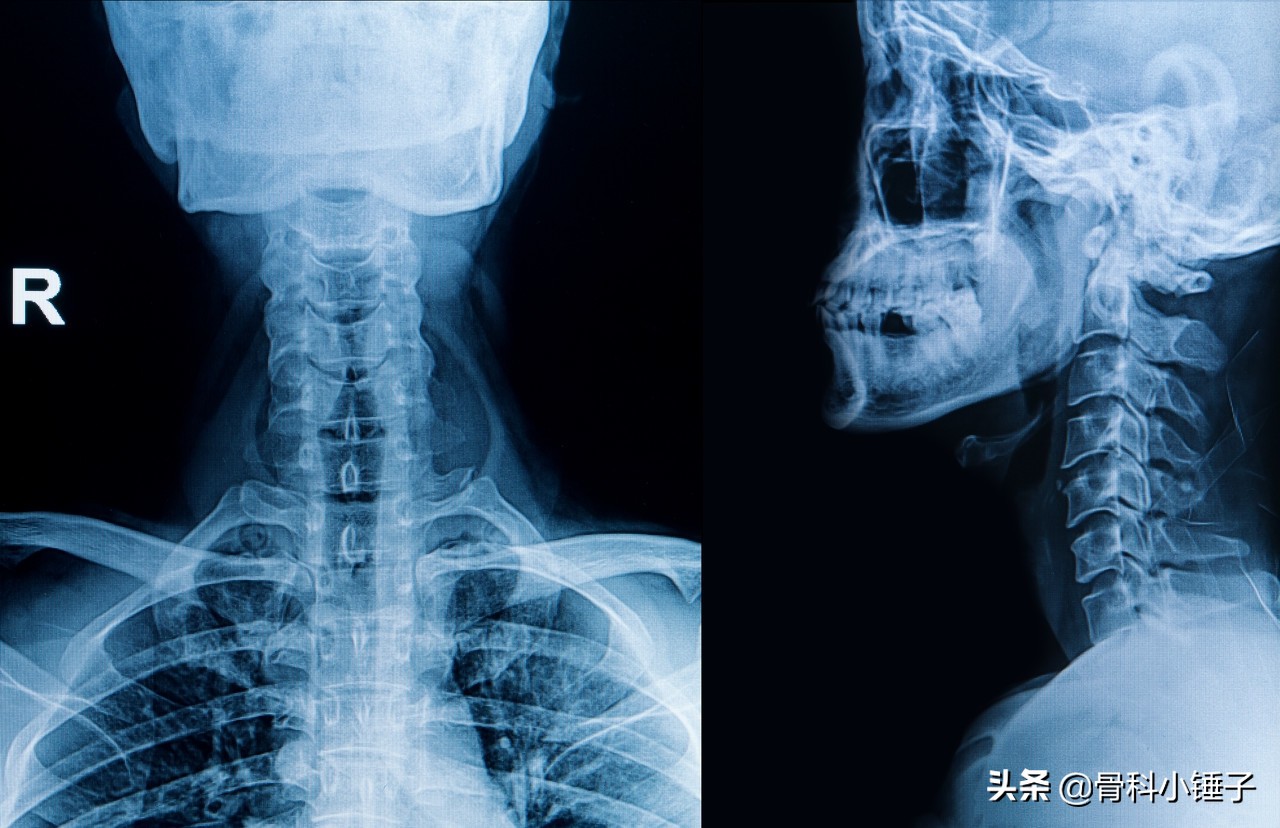

颈椎病又称颈椎综合征,是颈椎骨关节炎、增生性颈椎炎、颈神经根综合征、颈椎间盘脱出症的总称,是一种以退行性病理改变为基础的疾患。主要由于颈椎长期劳损、骨质增生,或椎间盘脱出、韧带增厚,致使颈椎脊髓、神经根或椎动脉受压,出现一系列功能障碍的临床综合征。一般表现为椎节失稳、松动;髓核突出或脱出;骨刺形成;韧带肥厚和继发的椎管狭窄等,刺激或压迫了邻近的神经根、脊髓、椎动脉及颈部交感神经等组织,引起一系列症状和体征。

依据其对脊髓、神经、血管等重要组织的压迫,颈椎病可分为神经根型颈椎病、脊髓型颈椎病、椎动脉型颈椎病、交感神经型颈椎病、食管压迫型颈椎病这五种。临床上以前两种最为常见,其具体诊断需要基于相应的临床表现及影像学表现作出。